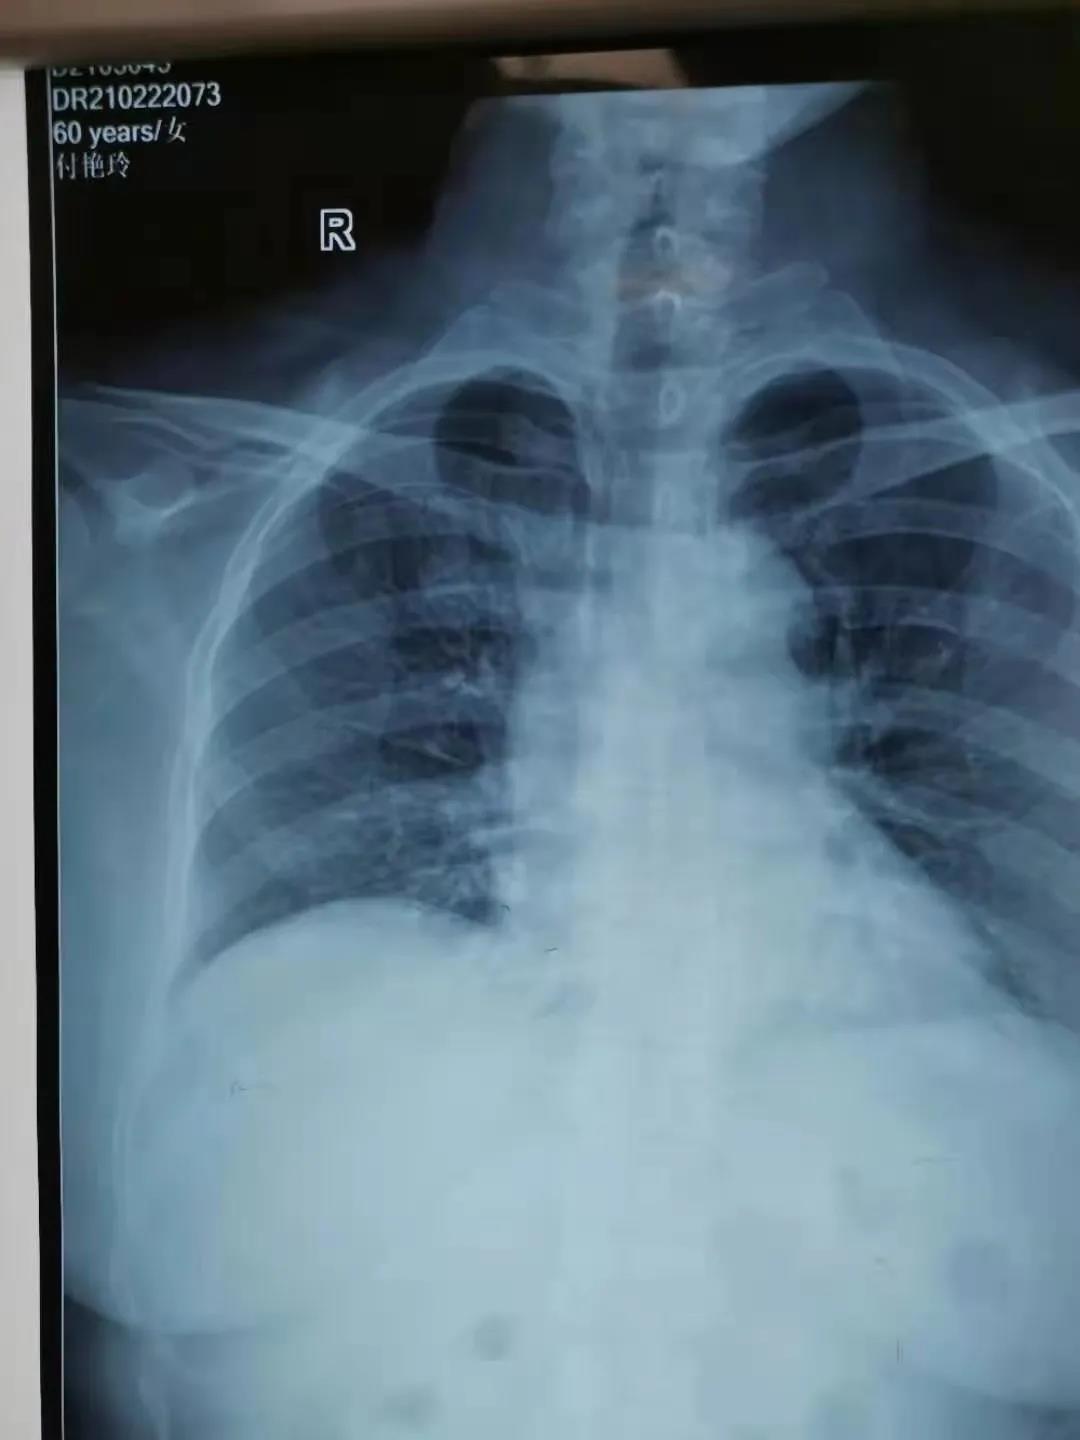

2月22日,由鄲城縣第二醫療健康服務集團鄲城縣中醫院腫瘤血液科護士長劉曉娟,護士丁星文、馬慧、張玉霞成立的靜脈治療專科小組,在經過了數例PICC置管中進行心電腔內(ECG)定位與x線下定位結果的比較后成功運用了ECG定位技術置管,此項技術的成功開展,標志著醫院PICC置管定位技術又上新臺階!

ECG腔內定位技術是一種在置管過程將特殊的心電導聯線聯接導管導絲和心電圖機,在送入導管過程中通過觀察心電圖上P波的特征性變化來判斷導管尖端的位置的方法,此項技術實現了在術中實時定位和調整導管頭端,達到精準定位PICC導管頭端位置的目的。

ECG定位技術通過一“進”兩“退”的方式(一進:當導管尖端到達CAJ時,可見高尖P波,進入右心房后P波雙向,由高尖再轉低;一退:當導管尖端從右心房退回上腔靜脈時P波恢復正常。再退:導管繼續后退2-3 cm到達最終正確的位置。)判斷導管尖端位置,及時糾正導管異位、極大的提高了導管尖端位置定位的準確性,避免了因反復調整導管位置所致的并發癥(靜脈炎、導管相關感染、血栓等)及因導管異位而重復拍片,保證了患者安全,提高了工作效率。③7